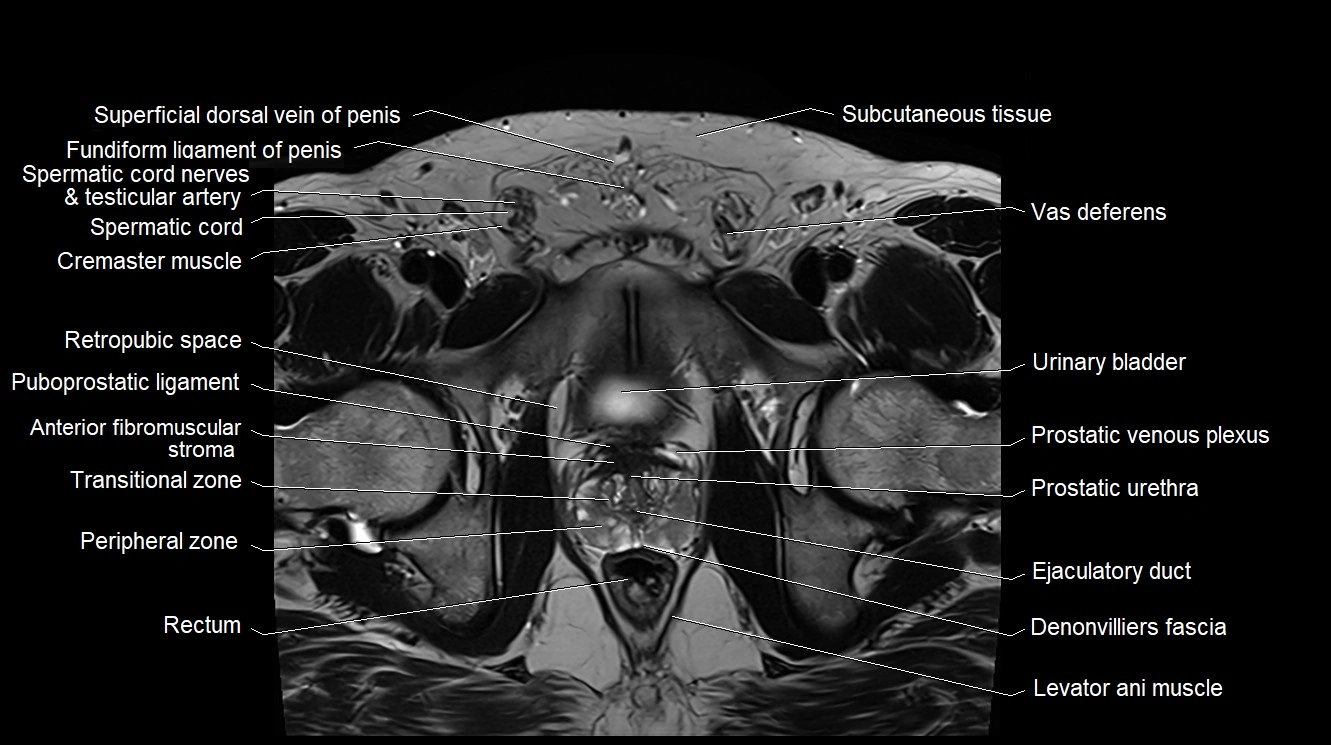

- Anterior Fibromuscular Stroma of prostate

- Cremaster muscle

- Ejaculatory duct

- Levator ani muscle

- Peripheral zone of prostate

- Prostatic urethra

- Puboprostatic ligament

- Rectoprostatic fascia (Denonvilliers' fascia)

- Rectum

- Retropubic space

- Transitional zone of prostate

- Urinary bladder

- Vas deferens